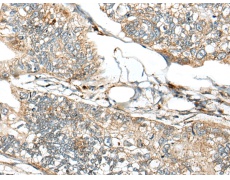

IHC positive control: |

Human gastric cancer and human thyroid cancer |